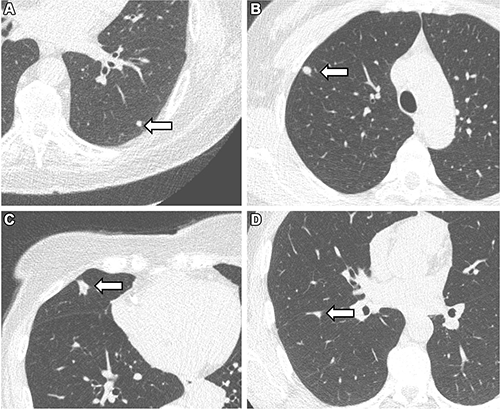

Representative chest low-dose CT images show lung nodules (arrows) and were included in the study. (A) A solid lung nodule, 82 mm3, in a 77-year-old male participant. (B) A clinically relevant nodule, 174 mm3, in a 55-year-old female participant. (C) An actionable nodule, 422 mm3, in a 79-year-old female participant. (D) A typical perifissural nodule, 183 mm3, in a 46-year-old male participant.